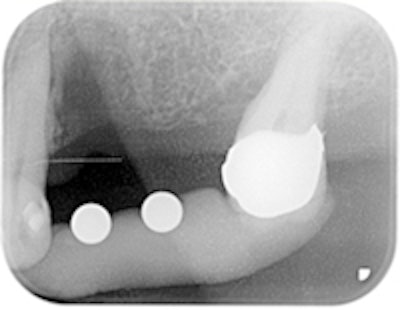

Figure 6 (bottom): Radiograph to control the implants after implantation.

The Spread-Condense screws were inserted in ascending order up to size 3 with the ratchet. Alternatively, a mechanical wrench was used for rotary insertion; however, this was preceded by the manual wrench (figure 5). Two Wital implants (Wieland Dental) were inserted with primary stability without further chip-producing preparation (figure 6). The treatment concluded with the augmentation of the autologous vestibular bone in tooth 24 and the filling of the defect bone up to the terminal molar.